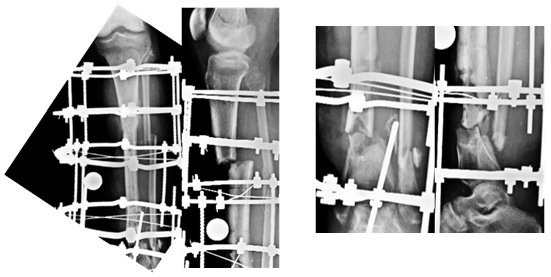

| X-ray at presentation |

| Central diaphysis of the Radius and Ulna sequestrated |